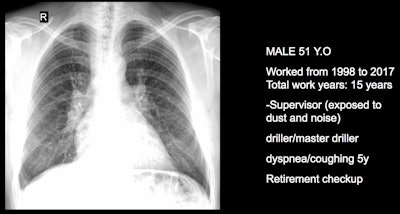

Three clinical cases courtesy of Luis Antonio Campos Calderon, MD.

The International Labor Organization (ILO) International Classification of Radiographs of Pneumoconioses is used for epidemiological studies, screening, and surveillance of workers exposed to dust in the workplace, and clinical purposes, and the National Institute for Occupational Safety and Health (NIOSH) B Reader Program certifies physicians in the ILO classification system. Each case should discuss its ILO classification and brief comments about the workflow, Campos Calderon noted.

The main diagnostic criteria are: Work history (minimum 10 years exposure to silica dust or other particles); chest x-ray (micronodular pulmonary fibrosis, coded according to ILO classification); progression (image profusion increases over time, even after exposure cessation; irreversibility (disease is progressive and irreversible, no stable pneumoconiosis over time).